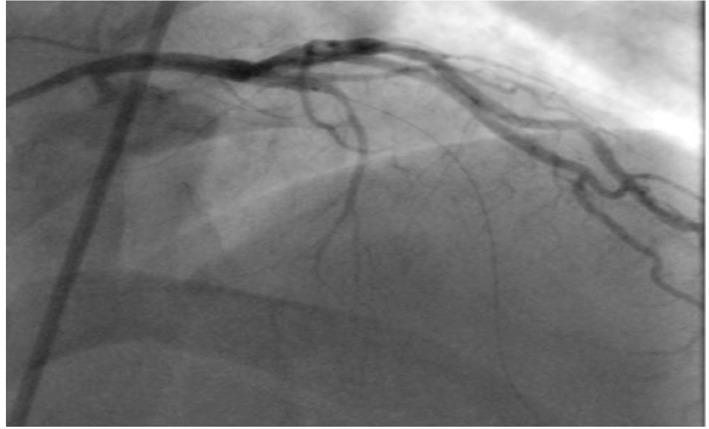

Although most of the patients presenting with ischemic heart disease have chest pains, there are other rare presenting symptoms like cardiac cephalgia. In this report, we present a case of acute coronary syndrome with an only presentation of exertional headache. It was postulated as acute presentation of coronary artery disease, due to previous history of similar presentation associated with some chest pains with previous left coronary artery stenting. We present an unusual case with cardiac cephalgia in a young patient under the age of 50 which was not reported at that age before. There are four suggested mechanisms for this cardiac presentation.

虽然大多数缺血性心脏病患者会出现胸痛,但也有其他罕见的症状,如心源性头痛。在本报告中,我们介绍了一例急性冠状动脉综合征,其唯一表现为劳力性头痛。由于既往有类似表现且伴有胸痛,曾行左冠状动脉支架置入术,故推测为冠状动脉疾病的急性表现。我们报告了一例50岁以下年轻患者的心源性头痛的罕见病例,此前该年龄段未见报道。关于这种心脏表现有四种推测机制。